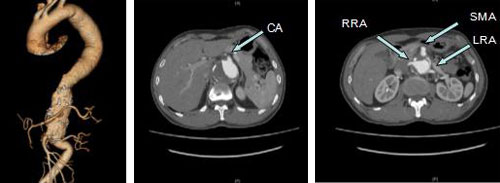

(CA:腹腔干,SMA:肠系膜上动脉,RRA:右肾动脉,LRA:左肾动脉)

该例患者,男,48岁,属II型胸腹主动脉瘤(crawford分型),瘤体最大径达7cm,累及腹腔干动脉、肠系膜上动脉、双肾动脉以及脊髓供血动脉。金星教授带领全科仔细讨论病情,研读患者影像资料,术前术后与麻醉手术科、心外科、重症医学科、输血科等多科室积极沟通交流,在多学科协助下由张十一教授治疗组(包括王默副主任医师、董典宁副主任医师、徐磊、孔祥骞主治医师)主刀,在气管插管全麻下,利用股动脉-股静脉体外循环系统完成胸腹主动脉瘤切除+人工血管置换术。术中采用单肺通气,螺旋体位行胸腹联合切口,经腹膜后入路,打开膈肌,显露胸主动脉及腹主动脉全程,完成动脉瘤切除、人工血管置换及腹腔干动脉、肠系膜上动脉、双肾动脉四支内脏动脉的重建。手术历时10小时。术后,患者在重症监护室的努力和医护人员的精心呵护下,先后闯过了出血、多脏器功能不全、感染等风险关口,最终康复并顺利出院。